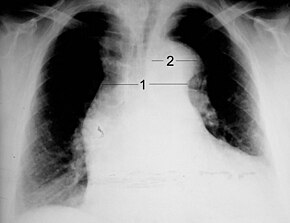

Chest radiography may demonstrate a change in shape of the thoracic aorta. Classically, new widening of the mediastinum is of moderate sensitivity for detecting an ascending aortic dissection; however, this finding is of low specificity, as many other conditions can cause apparent widening of the mediastinum.

There are several other associated radiographic findings:

Importantly, about 12 to 20% of aortic dissections are not detectable by chest radiograph; therefore, a "normal" chest radiograph does not rule out the condition. If there is high suspicion, a more sensitive imaging test (CT angiogram, MR angiography, or transesophageal echo) may be warranted.